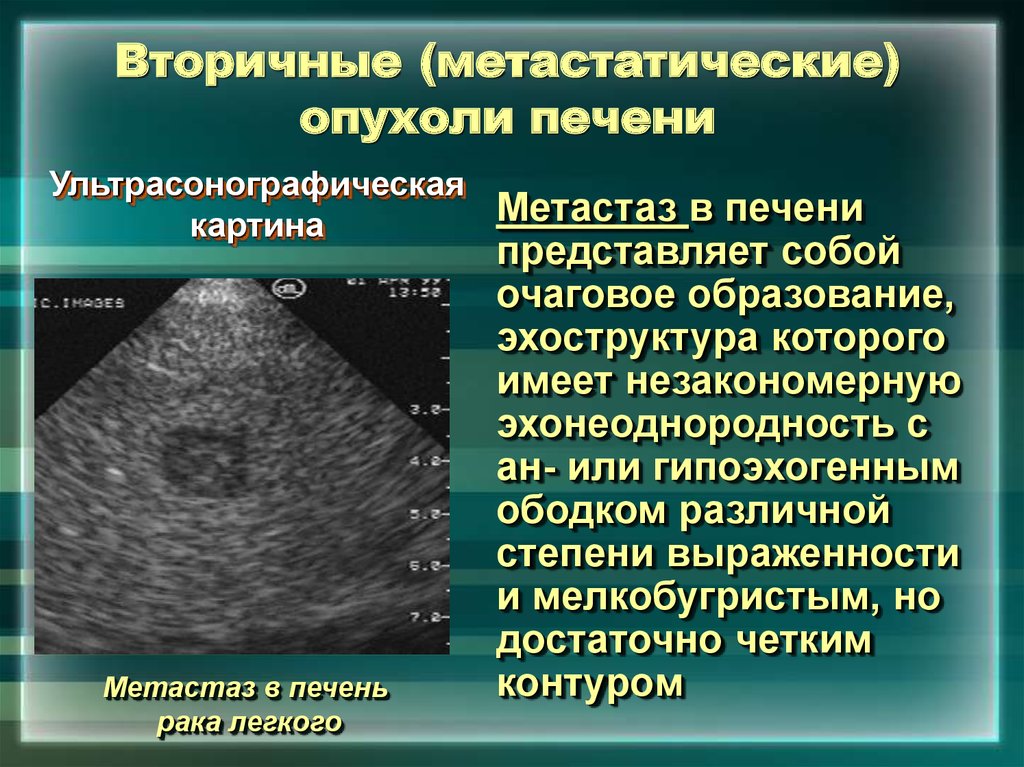

Метастатические поражения печени в ультразвуковом изображении характеризуются